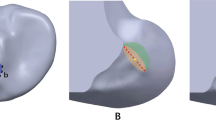

We found that there were common trends in stress patterns around the inner orifice of femoral tunnel regardless of drilling method. At 0° of flexion, the highest stress was seen on the anterior margin of the inner orifice of the tunnel where the contact between the bone and the graft occurred in both group. At 90° and 135° of flexion, the site of the highest stress moved to the posterior part of the inner orifice. Meanwhile, high stress concentration was also monitored around the outer orifice of the tunnel where the tendon was fixated in both groups. In this area, the stress concentration was more predominant in the TP group than in the modified TT group at all flexion angles. Overall stress patterns are shown in Fig. 3.

Patterns of stress distribution at different flexion angles in the knee models with the TP or the modified TT technique. At 0° of flexion, the highest stress was seen on the anterior margin of the inner orifice of the tunnel in both groups. At 90° and 135° of flexion, the site of the highest stress moved to the posterior part of the inner orifice (A). The maximal stress concentration was also monitored around the outer orifice of the tunnel where the tendon was fixated in both groups (B). These figures are from a single representative specimen (TP group: upper column, modified TT group: lower column)